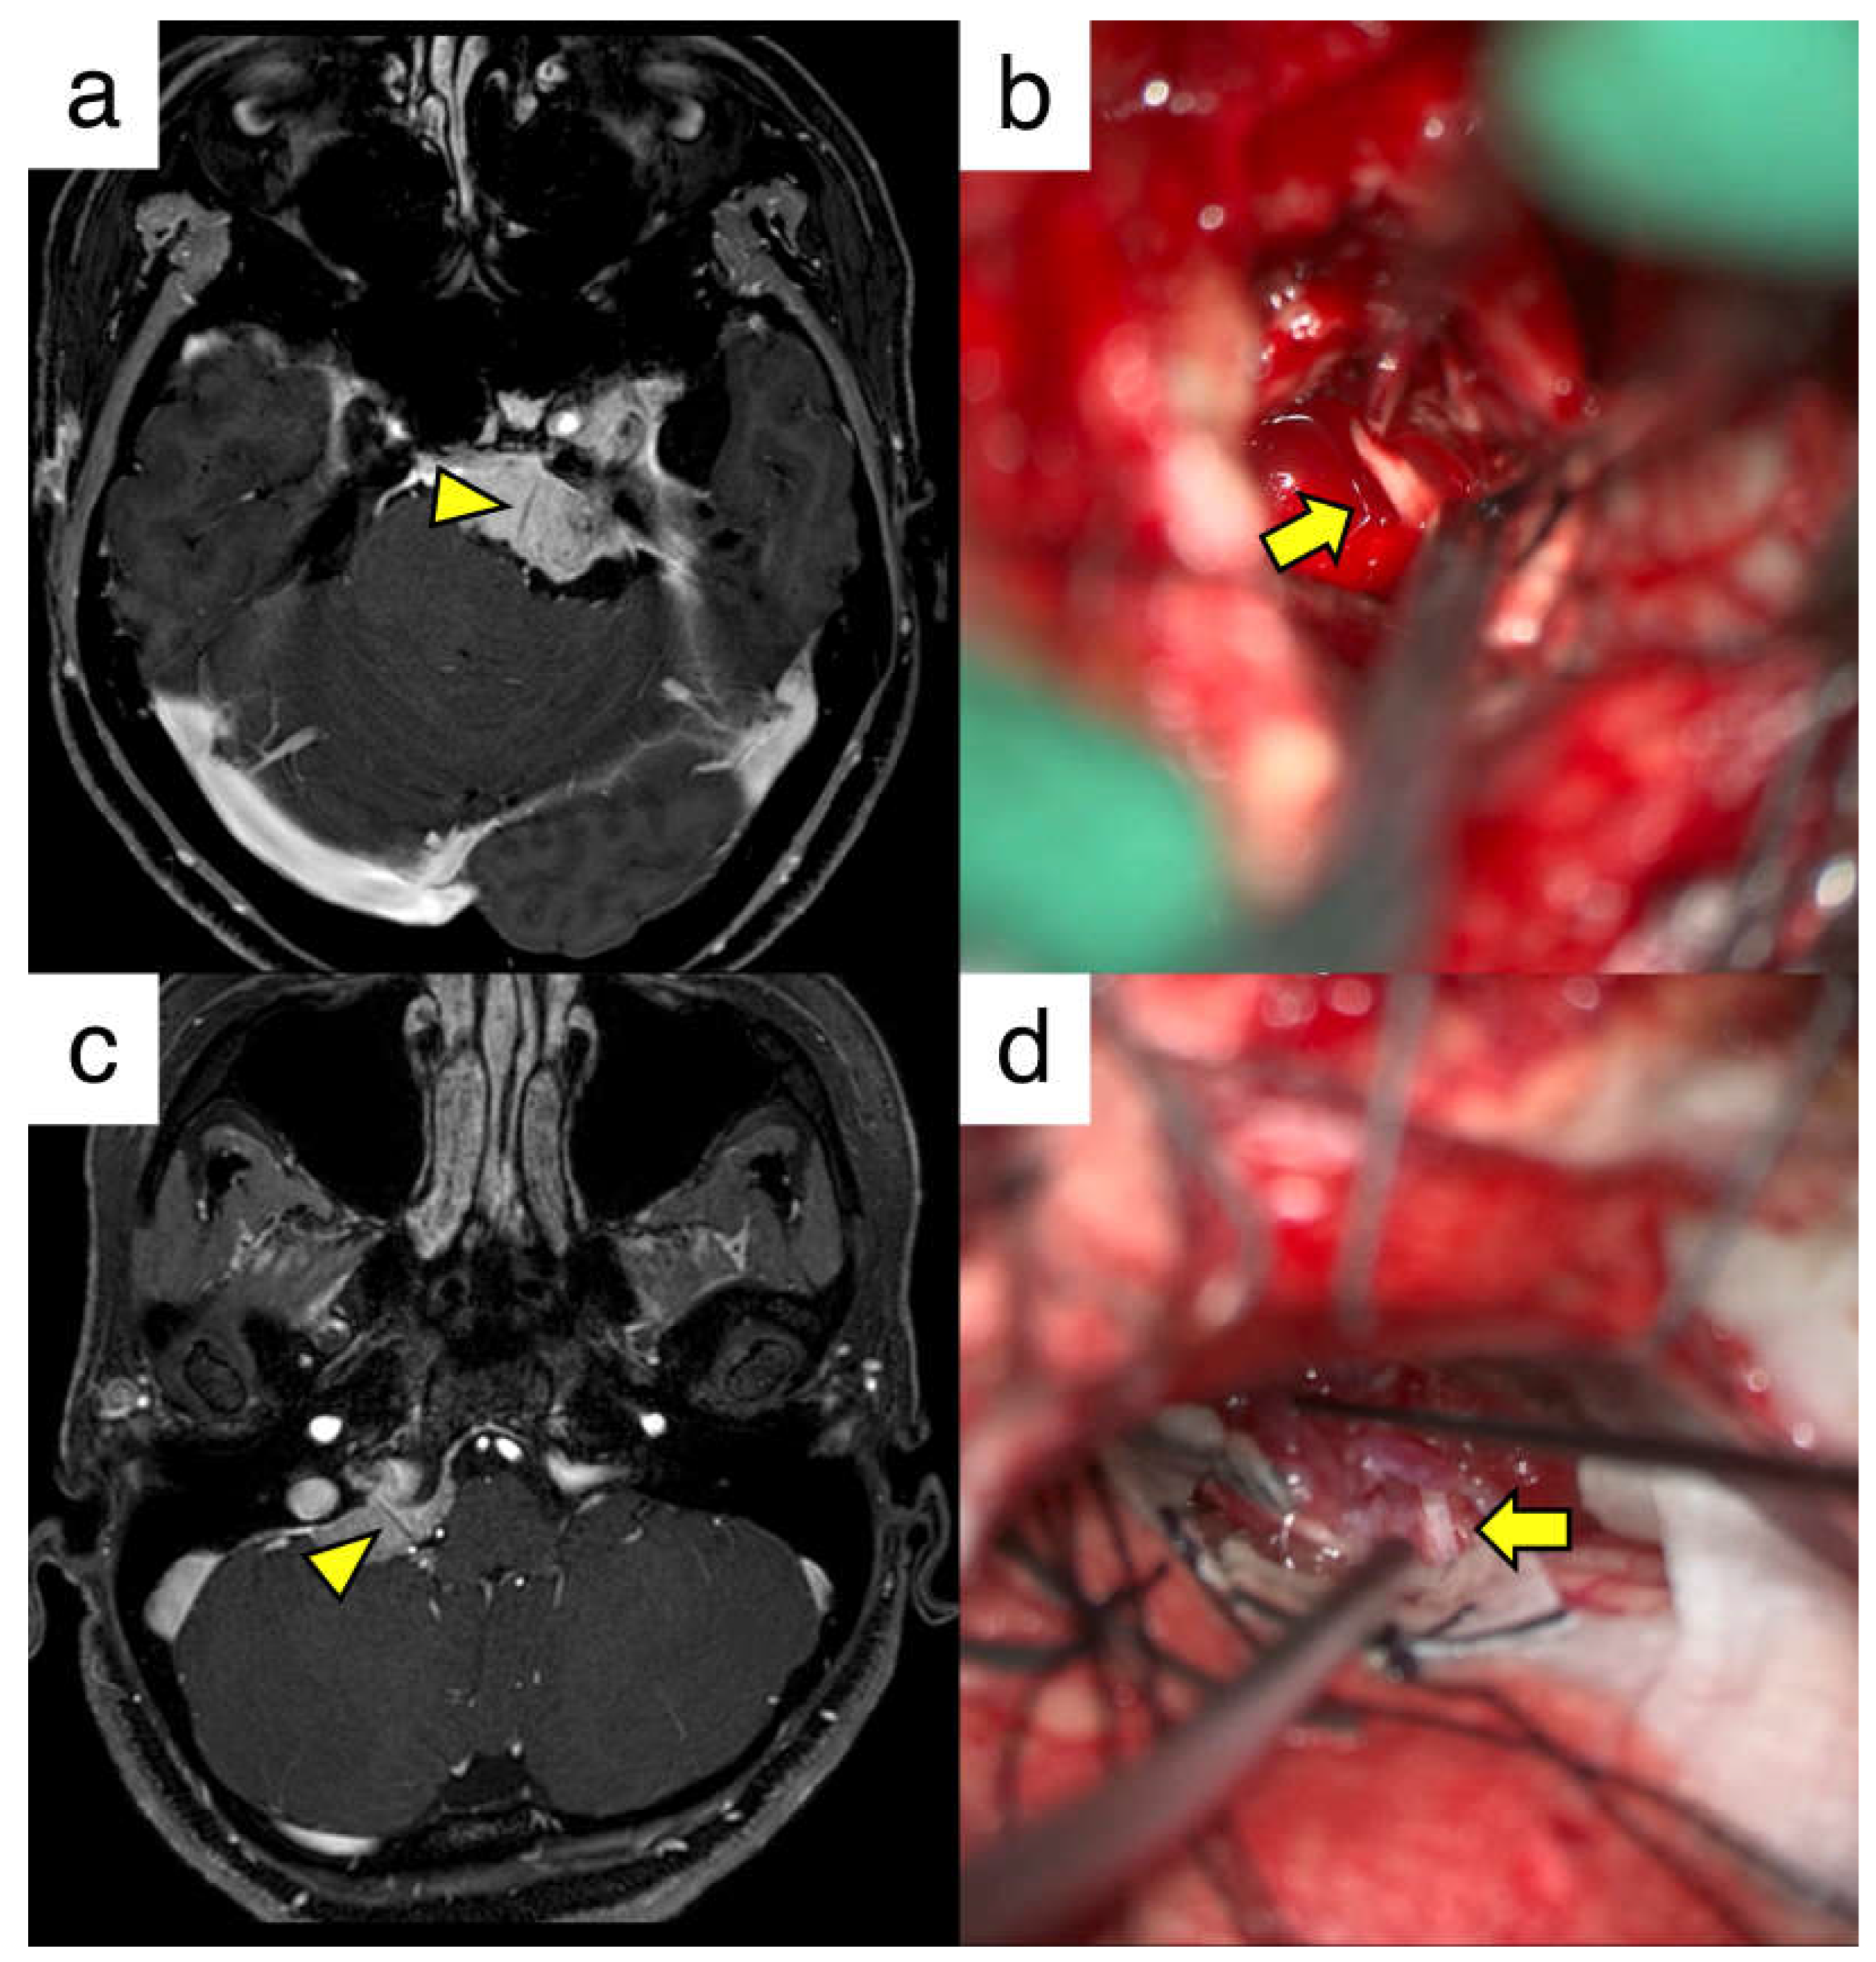

5. Cranial Nerves Penetrating Skull Base Tumors

| Case | Age | Sex | Attachment | Contrast Defect | Intraoperative Findings of CNs | Pathology |

|---|---|---|---|---|---|---|

| 1 | 47 | F | Petrous | LCNs | Penetrated | Meningothelial |

| 2 | 75 | F | Foramen magnum | LCNs | Penetrated | Transitional |

| 3 | 48 | F | Petroclival | V | Penetrated | Meningothelial |

| VI | Not observed | |||||

| VII-VIII | Not observed | |||||

| 4 | 78 | M | Petroclival | V | Penetrated | Meningothelial |

| VI | Penetrated | |||||

| 5 | 70 | M | Petroclival | V | Penetrated | Clear cell |

| 6 | 48 | F | Petrotentorial | V | Penetrated | Meningothelial |

| 7 | 74 | F | Petrotentorial | V | Penetrated | Transitional |

| 8 | 45 | F | Jugular tubercle | LCNs | Penetrated | Meningothelial |

| 9 | 61 | F | Petroclival | VI | Penetrated | Meningothelial |

| 10 | 35 | F | Petrous | LCN | Penetrated | Meningothelial |